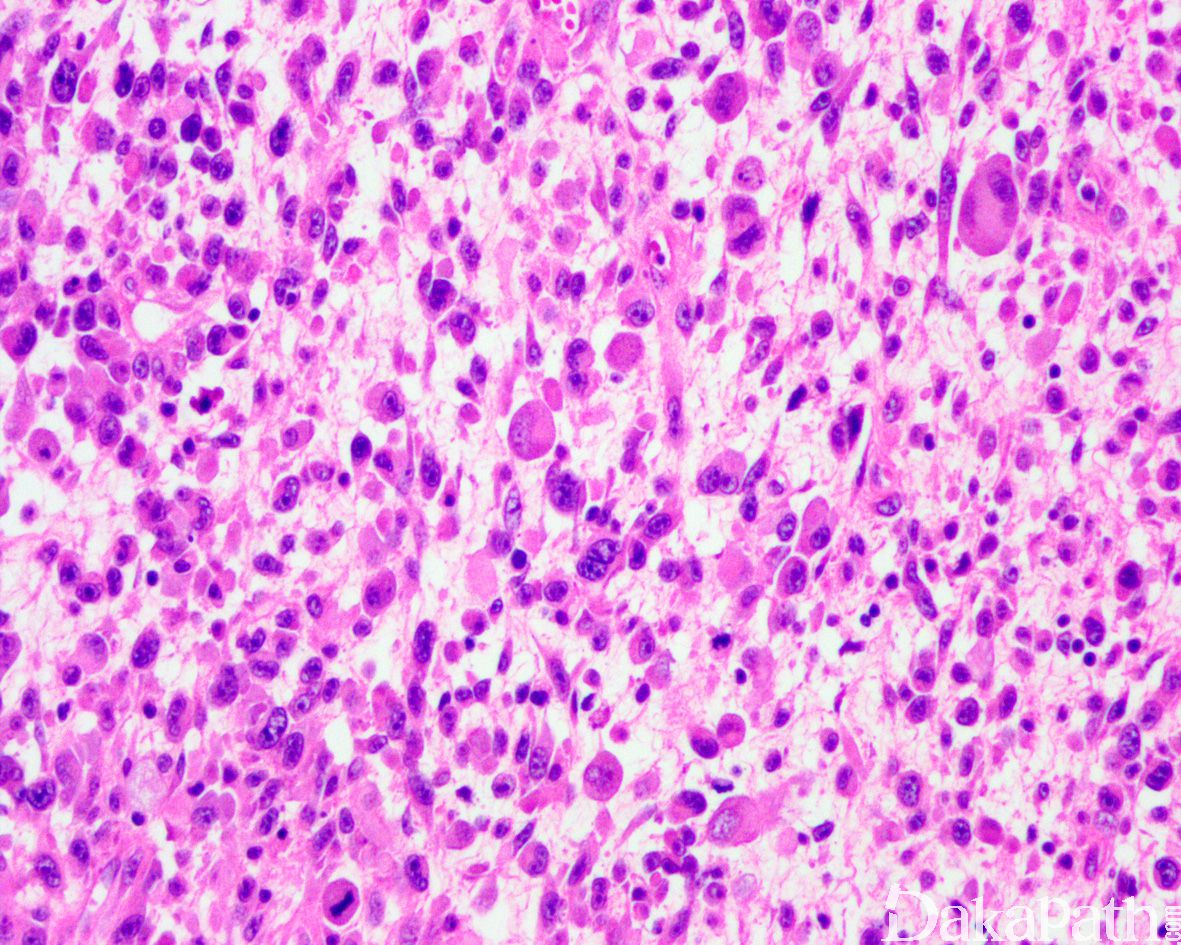

部分细胞呈蝌蚪状、带状或网球拍状,胞质呈深嗜伊红色,外形不规则,一些细胞大而畸形,具深伊红色胞浆,这类细胞具有诊断价值;

少数病例瘤细胞胞质丰富,因中间丝聚集在核旁而呈包涵体样,核大,圆形和卵圆形,常偏位,染色质空泡状,可见明显的核仁;

部分区域可见瘤巨细胞或多核巨细胞,类似多形性未分化肉瘤;